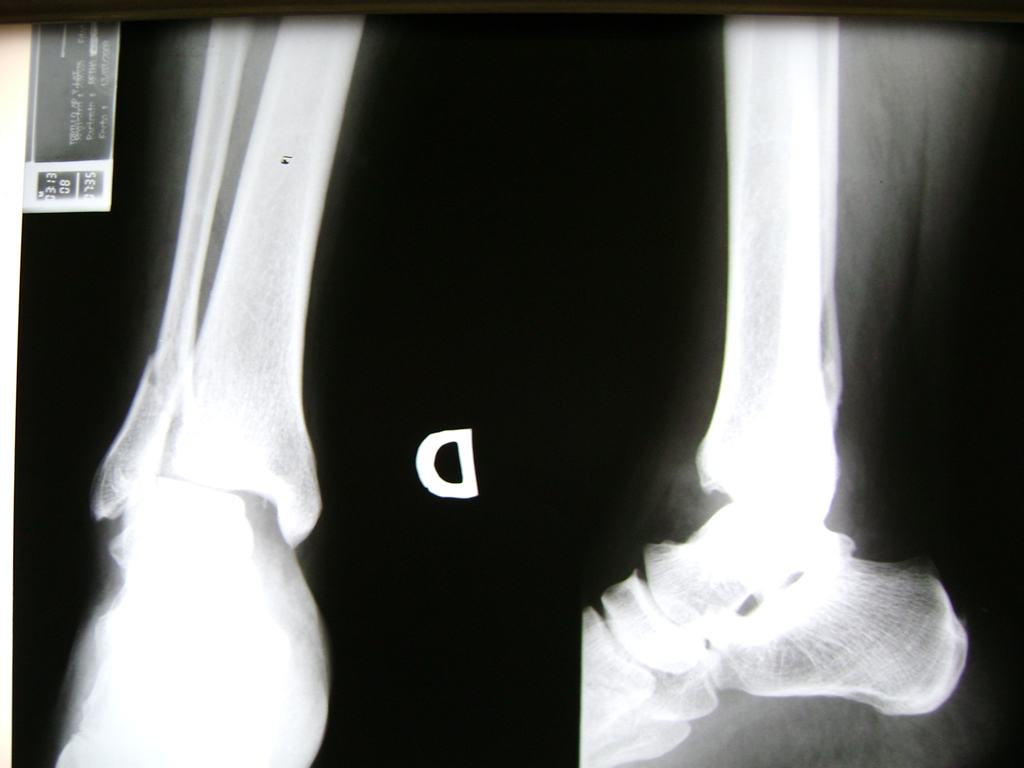

Una fractura de tobillo es la rotura de uno o más de los huesos del tobillo. Estas fracturas pueden ser:

- Parciales (el hueso está sólo parcialmente fisurado, no del todo).

- Completas (el hueso está perforado y está en 2 partes).

- Los extremos de los huesos están desalineados entre sí (desplazados).

Cuando se necesita cirugía, es probable que esta implique el uso de clavijas de metal, tornillos o placas para sostener los huesos en su lugar mientras la fractura se consolida. Los elementos de soporte pueden ser temporales o permanentes.